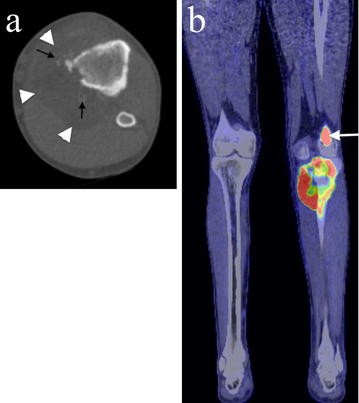

Positron emission tomography with fluorodeoxyglucose (FDG) integrated with computed tomography (PET/CT) confirmed an ill-defined proximal tibial lesion with medial cortical destruction and a large soft tissue mass containing areas of fat attenuation and ossification (Fig. 3a). The tumour showed marked FDG uptake with a standardised uptake value (SUV) of 17.1 and a band of relative photopaenia in the region of the undisplaced transverse pathological fracture. A further focus of markedly increased FDG uptake with an SUV of 13.5 was seen in a lateral distal femoral lesion which was presumed to represent a metastasis (Fig. 3b). Eight small bilateral pulmonary nodules (maximum 4 mm) were also noted on the PET/CT scan consistent with lung metastases. There was no lymphadenopathy, and no fat or other soft tissue lesion was noted.

Axial CT and PET/CT imaging of the proximal tibial lesion. a Axial CT imaging shows medial cortical destruction and a large soft tissue mass containing areas of fat attenuation (white arrowheads) and ossification (black arrows). b A coronal fused PET/CT image shows there is marked FDG uptake in the proximal tibial tumour as well as in a lateral distal femoral metastasis (white arrow). No other lipomatous lesion or tumour is present